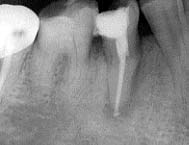

初診時 パノラマ 「456 術中Dental写真

34歳 男性 「45 2根管,「6 4根管

口腔内全体にカリエスによる歯冠崩壊が著しく、清掃状態も不良であった。 残根状態の歯全てと根管治療済みの歯全てに根尖病巣が認められた。左下56の根尖付近を 中心に軽度な腫脹があり、疼痛の原因が56根尖病巣によるものであることが推測された。

浸潤麻酔の上、「56の根管を開始したが、いずれの歯も歯髄腔は狭窄の上、弯曲しており 作業は難航を極めた。おまけに術中のDental写真により根管数の異常が確認された。悪戦苦闘の 末根管の拡大および清掃が完了。根尖部からの排膿は認められなかったが、解放状態で内服薬を 投与して当日の治療を終了した。  翌日、根尖部の腫脹と疼痛が消失し、経過が良好であったことから根管充填を行い次のステップ に移行した。尚、重傷のカリエスにより歯髄炎の疑われた「4は特に症状がないので咬合保全の 意味を含めて「56補綴完了後に行う予定である。

下顎6番の4根管は比較的多く存在するが、4番・5番の2根管は比較的稀である。しかも 4番・5番が2本とも2根管であることはもっと稀なケースである。 根管数が多ければ作業量はそれだけ多くなる以上に細く弯曲した根管を拡大・清掃する作業は 難航を極めることはいうまでもない。